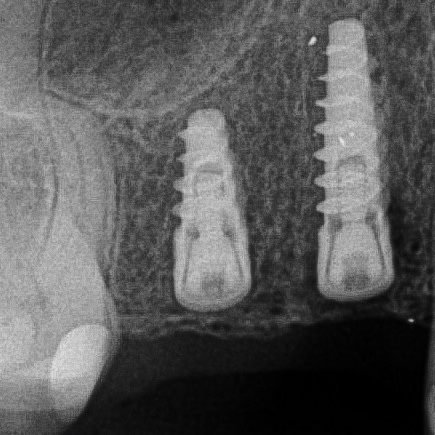

Looking back at a case I did a few years ago, I’ve realized how much my approach has evolved.

I placed two implants in the posterior region using guided surgery. At the time, I chose a tissue punch technique because there was plenty of keratinized tissue, and it felt like the most minimally invasive option. The implants healed well, and the…